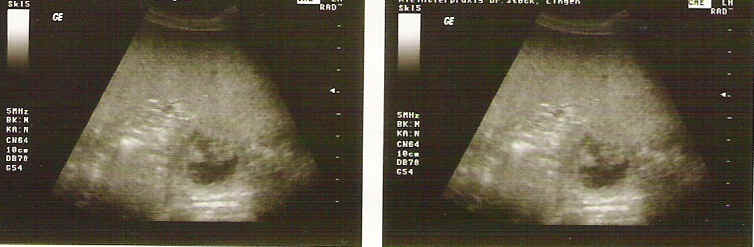

Brisby van Noort Ultraschallbilder " D - Wurf "

Vater: Broncor v. Speichersee Mutter: Brisby van Noort

Ultraschallbilder der Hündin Brisby van Noort, erstellt am 28. Tag.